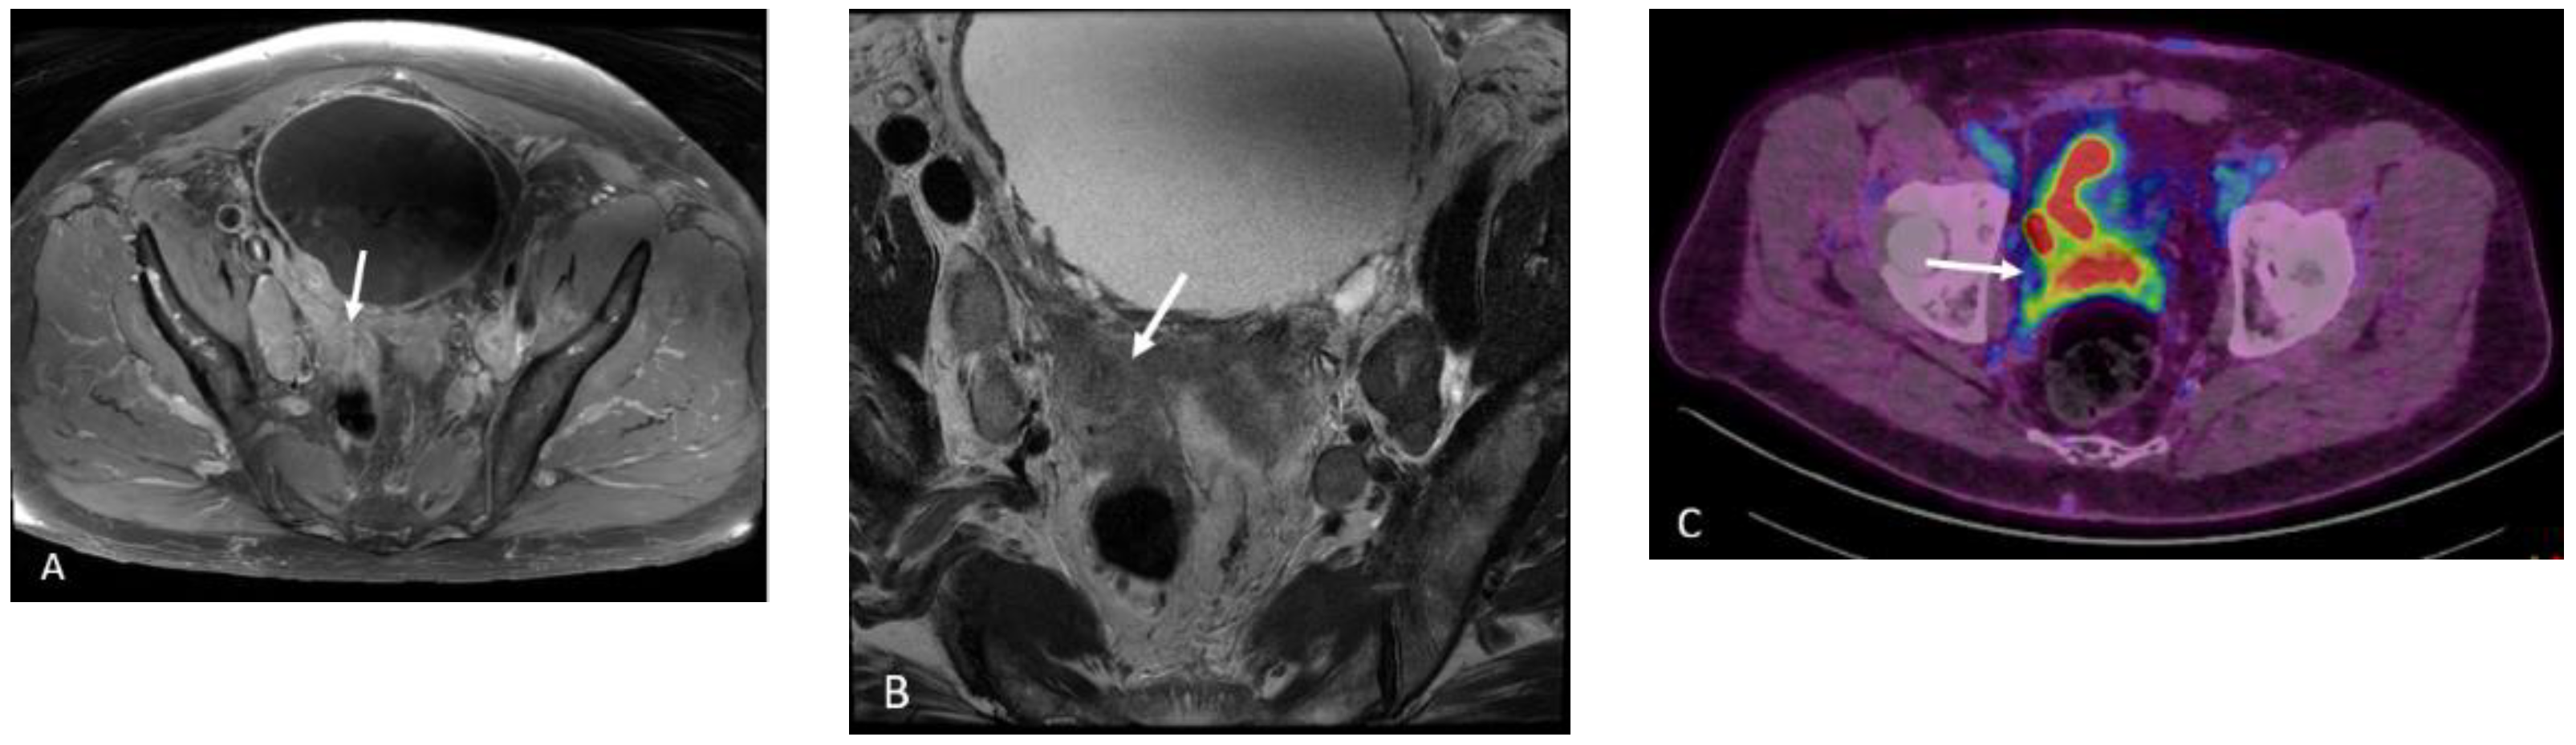

Detection of Loco-Regional Disease and Distant Metastases

1.9.3. Pearls and Pitfalls

- Giesel, F.L.; Sterzing, F.; Schlemmer, H.P.; Holland-Letz, T.; Mier, W.; Rius, M.; Afshar-Oromieh, A.; Kopka, K.; Debus, J.; Haberkorn, U.; et al. Intra-individual comparison of 68Ga-PSMA-11-PET/CT and multi-parametric MR for imaging of primary prostate cancer. Eur. J. Nucl. Med. Mol. Imaging 2016, 43, 1400–1406. [Google Scholar] [CrossRef] [PubMed] [Green Version]

- Eiber, M.; Weirich, G.; Holzapfel, K.; Souvatzoglou, M.; Haller, B.; Rauscher, I.; Beer, A.J.; Wester, H.J.; Gschwend, J.; Schwaiger, M.; et al. Simultaneous 68Ga-PSMA HBED-CC PET/MRI Improves the Localization of Primary Prostate Cancer. Eur. Urol. 2016, 70, 829–836. [Google Scholar] [CrossRef] [PubMed]